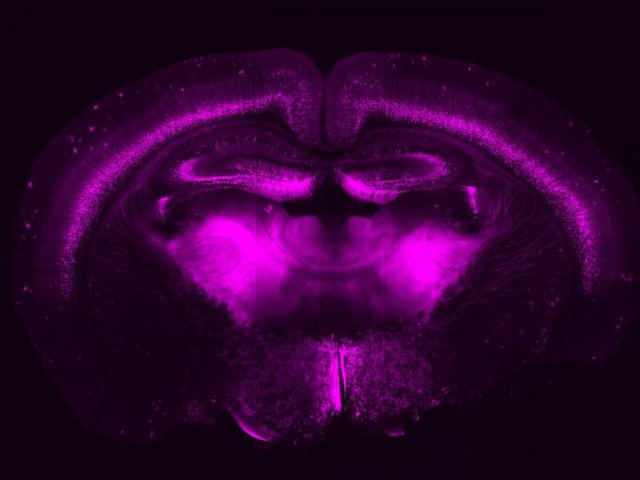

Науковці показали, як мозок концентрує увагу

Дослідники з Квінслендського університету (Австралія) за допомогою маніпуляцій з пірамідальними нейронами продемонстрували, як їх активність пов'язана з холінергічною системою. Праця опублікована в журналі Neuron.

Холінергічна система – сукупність нейронів, що концентруються в базальних відділах переднього мозку. Вона проектує аксони по всій корі головного мозку і секретує ацетилхолін. Вона ж регулює сенсорне сприйняття, а її пошкодження у тварин призводить до порушення пам'яті і когнітивних здібностей.

Вчені вважають, що система відповідальна за управління увагою, але не знають, як саме вона виконує цю функцію. Австралійські біологи вирішили виявити її зв'язок з пірамідальними нейронами L5B (layer 5B), тому що ті активні у щурів і мишей при виконанні різних завдань.

Учені використовували метод оптогенетики, заснований на впровадженні в мембрану нейронів опсинів, що реагують на світло. Так автори праці могли регулювати діяльність холінергічної системи.

Коли пірамідальні нейрони перебували в стані спокою, сигнали холінергічної системи ніяк на них не впливали. Однак, якщо нейрони збуджували через дендрити, система тільки посилювала їх активність. Лі Флетчер (Lee Fletcher), який брав участь в дослідженні, сказав, що холінергічна система буцімто давала їм сигнал до старту.

Біологи вважають, що саме цей механізм лежить в основі зосередження уваги гризунів на конкретному завданні. Вони також припускають, що в людському мозку відбувається той же процес, дозволяючи нам утримувати фокус на чомусь одному і зберігати пильність.